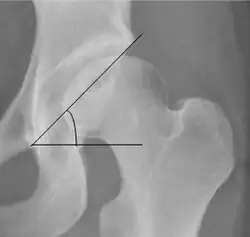

| Sharp angle | ![]() |

Acetabular slope | <45°

|